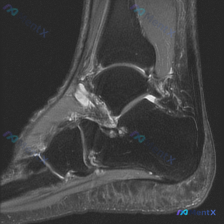

看到这个有意思的病例,整理了完整的分析思路分享给大家。 病例核心影像信息 这是一张踝关节MRI矢状位T1加权图像,原始疑问是观察到「软组织液体」,系统影像评估结果如下: 1. 骨性结构:各骨皮质连续,无骨折、骨质破坏,骨髓信号均匀,关节对位正常,关节面光滑,无明显骨赘或软骨下囊肿 2. 韧带肌腱:跟...

病例影像分析分享 今天整理了一例踝关节MRI的分析思路,原始提示看到「软组织积液」,我们一步步来拆解: 病例影像基本信息 这是一例踝关节MRI冠状位T2加权像,我们先做系统性解剖评估: 1. 骨与关节:胫距关节、距下关节间隙正常,关节面平滑,胫骨远端、距骨、跟骨骨髓信号均匀,没有骨赘、软骨下囊肿、骨...